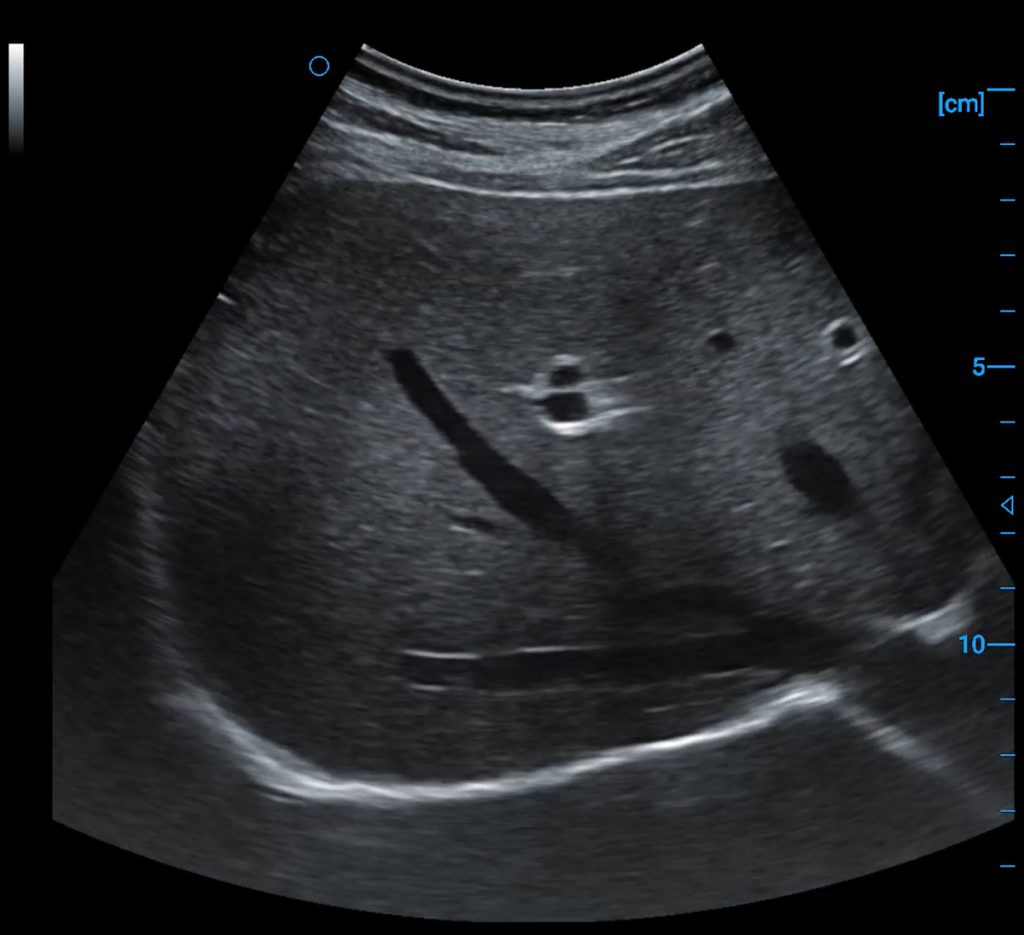

Liver B image

Liver blood flow